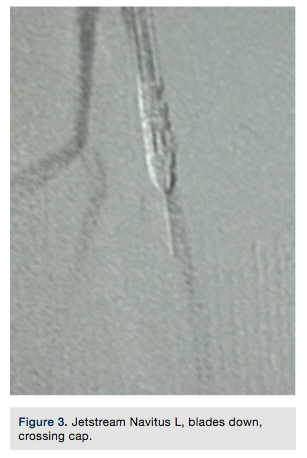

A 7 French x 65 cm Pinnacle Destination sheath (Terumo) was advanced where the tip was placed in the mid right SFA. Systemic anticoagulation with heparin was given and the patient had been pretreated with aspirin and clopidogrel. Standard chronic totalocclusion (CTO) crossing techniques were used to try to gain access across the 100% occluded distal right SFA beginning with a 0.0350-inch Minnie Support Catheter (Vascular Solutions, Inc) and a soft, angled Glidewire (Terumo). Failure to cross prompted advancing to a stiff, angled Glidewire (Terumo), and then a Hi-Torque Supracore 0.035-inch Support Wire (Abbbott Vascular) within the support catheter. Escalation in wire stiffness resulted in inability to pierce the proximal cap. A Frontrunner Catheter (Cordis) was used unsuccessfully in a further attempt to cross (Figure 2). Finally, a 2.4 to 3.4 mm Jetstream Navitus L (Bayer Interventional) debulking atherectomy device was advanced to the proximal cap of the lesion over a Spartacore 0.014-inch long guide wire (Abbott Vascular), with the distal flexible tip of the guide wire excised and its blunt, firm tip protruding out of the tip of the Jetstream catheter. The blunt, sharp wire tip was imbedded into the proximal CTO cap and the Jetstream Navitus was activated with the blades down to enter the lesion. After crossing the proximal cap, the atherectomy device was removed and the Frontrunner catheter crossed the CTO segment, allowing us

to gain purchase in the distal vessel within the true lumen. Placement was confirmed with a hand injection angiogram into the popliteal artery. There was no evidence of dissection. Routine debulking atherectomy was performed with the Jetstream Navitus 2.4 to 0.4 mm device with blades down (Figure 3) and blades up across the occluded segment (Figures 4-5) over the Spartacore wire. Balloon dilation was then performed with 5.0 x 80 mm and 6.0 x 80 mm Chocolate balloons (Trieme Medical)